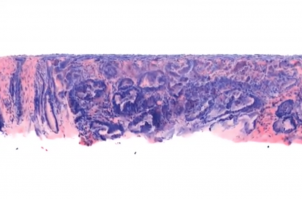

It conserves valuable tissue for genetic testing and diagnosis, quickly and accurately images the irregular surfaces of large clinical specimens, and allows pathologists to zoom in and "see" biopsy samples in three dimensions.

"The tools we use in pathology have changed little over the past century," said co-author Dr. Nicholas Reder, chief resident and clinical research fellow in UW Medicine's Department of Pathology. "This light-sheet microscope represents a major advance for pathology and cancer patients, allowing us to examine tissue in minutes rather than days and to view it in three dimensions instead of two -- which will ultimately lead to improved clinical care."

Current pathology techniques involve processing and staining tissue samples, embedding them in wax blocks, slicing them thinly, mounting them on slides, staining them, and then viewing these two-dimensional tissue sections with traditional microscopes -- a process that can take days to yield results.

By contrast, the UW open-top light-sheet microscope uses a sheet of light to optically "slice" through and image a tissue sample without destroying any of it. All of the tissue is conserved for potential downstream molecular testing, which can yield additional valuable information about the nature of the cancer and lead to more effective treatment decisions.

"Slide-based pathology is still an analogue technique, much like radiology was several decades ago when X-rays were obtained on film. By imaging tissues in 3-D without having to mount thin tissue sections on glass slides, we are trying to transform pathology much like 3-D X-ray CT has transformed radiology," Liu said. "While it is possible to scan microscope slides for digital pathology, we digitally image the intact tissues and bypass the need to prepare slides, which is simpler, faster and potentially less expensive."